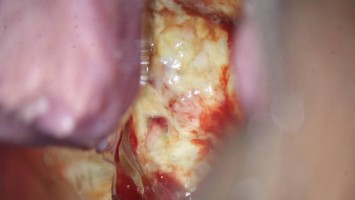

Anhaltende vaginale Blutung zehn Monate nach Re-Sectio

Eine 31-jährige, stillende Patientin stellt sich mit zunehmend übelriechendem Vaginalausfluss und anhaltender Schmierblutung vor. Zehn Monate zuvor hatte sie per Re-Sectio entbunden, bei der es intraoperativ zu einer Uterusatonie kam. Nun zeigt die Vaginalsonographie einen dramatischen Befund, der sofortiges Handeln erfordert.

e.Med Interdisziplinär Icon, Search Icon, Transvaginaler Ultraschall/© Graphicroyalty / stock.adobe.com (Symbolbild mit Fotomodellen), Glaszellentumor der Gebärmutter/© Boeker M et al. / all rights reserved Springer Medizin Verlag GmbH, Extrauteringravidität /© Tsitlakidis I et al. / all rights reserved Springer Medizin Verlag GmbH, Bilaterale ausgedehnte zylindrische Bronchiektasen/© Düsterhöft D et al. / all rights reserved Springer Medizin Verlag GmbH, CT des Uterus einer 47-Jährigen /© Rizos A et al. | all rights reserved Springer Medizin Verlag GmbH, MRT des Beckens: Uterus und Ovarialtumoren/© Hosten AK et al. / all rights reserved Springer Medizin Verlag GmbH, Digitales Blutdruckmessgerät/© Kotchakorn / Stock.adobe.com (Symbolbild mit Fotomodell), Frau tastet ihre Brust ab/© Pheelings Media / Getty Images / iStock (Symbolbild mit Fotomodell), Feten von siamesischen Zwillingen/© Zahn E et al. / all rights reserved Springer Medizin Verlag GmbH, MRT einer intrakavitären Raumforderung/© Lattermann M et al. doi.org/10.1007/s00761-025-01733-0 unter CC-BY 4.0, Aufnahme nach Resektion der Extrauteringravidität/© Antonia Jörger